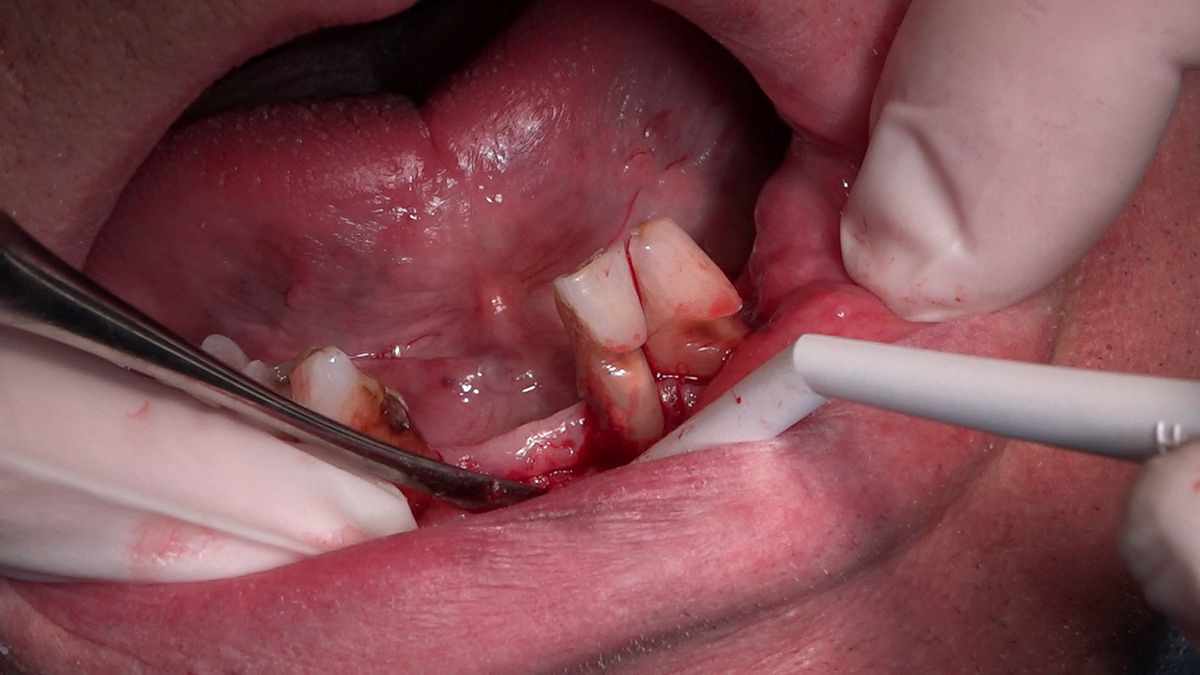

PRACTICULUM IMPLANTOLOGII - SEZON X - SESJA 4 - GRUPA B